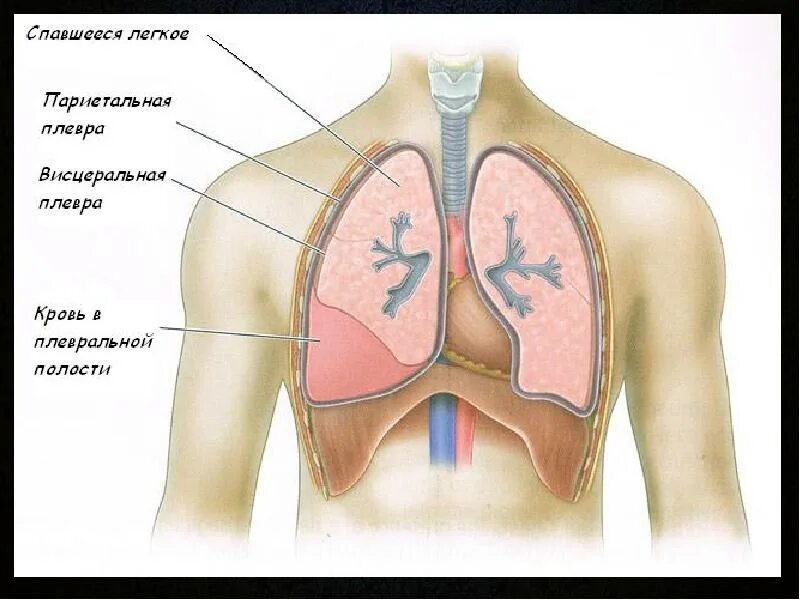

Почему в легких